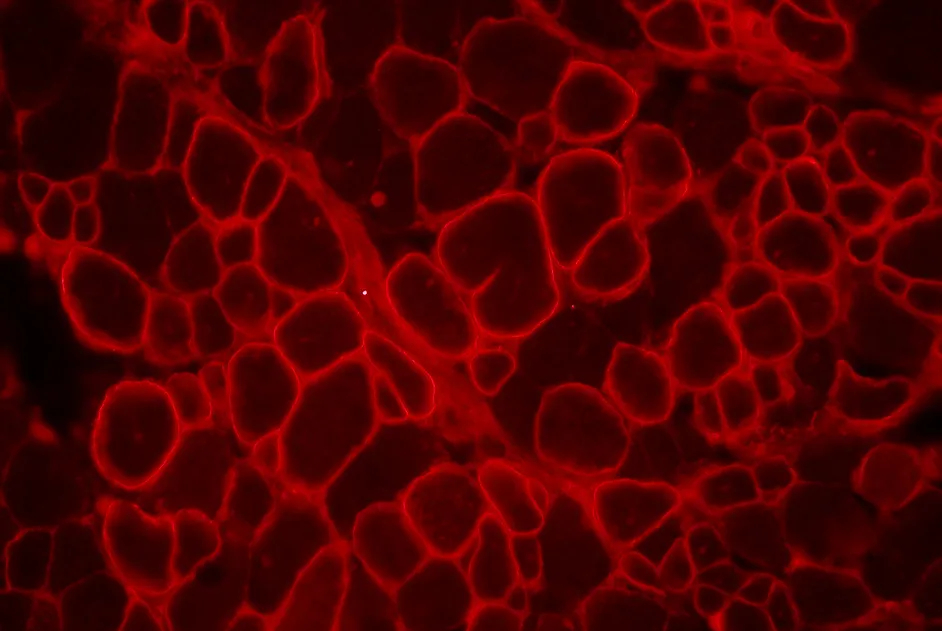

Dans un article publié en mai 2012, une équipe israélienne a étudié les effets de l'administration de losartan à des souris modèles de MDC1A, dy2J/dy2J. La force musculaire et la fibrose ont été significativement améliorées par rapport à celles des souris sous placebo.